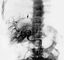

Диагноз ставят на основании эпидемиологического анамнеза (пребывание больного в эндемическом по альвеолярном эхинококкозе очаге), характерных клинических симптомов и специальных тестов — эозинофилии, увеличения СОЭ, диспротеинемии, положительной внутрикожной пробы Касони (при повторной постановке возможен анафилактический шок!), реакции латекс-агглютинации. При обзорной рентгенографии области печени в зоне паразитарного узла выявляются обызвествления в виде «известковых брызг» (рис. 2). Наиболее точные диагностические и топографические данные получают при ультразвуковом исследовании (рис. 3) и компьютерной рентгеновской томографии печени (рис. 4). Реже для уточнения характера, локализации и величины паразитарных узлов печени используют ее сканирование, лапароскопию, ангиогепатографию (рис. 5), пункционную биопсию. А. печени необходимо дифференцировать с циррозом печени, раком и эхинококкозом печени.